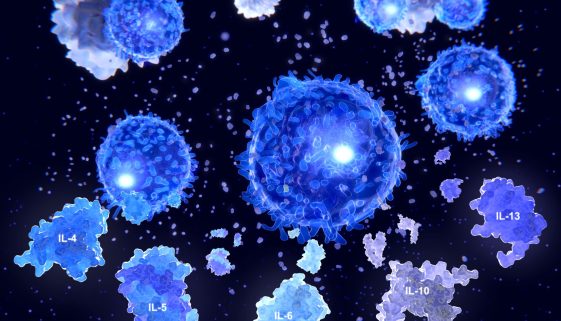

تعتبر حساسية العيون من المشاكل الصحية الشائعة التي يعاني منها العديد من الأشخاص في مختلف أنحاء العالم. وتعرف هذه الحالة بتهيج العينين نتيجة تفاعل الجهاز المناعي مع المواد المحفزة، مثل الغبار وحبوب اللقاح والدخان. يهدف هذا المقال لتقديم نصائح وتعليمات تثقيفية حول علاج حساسية العيون والوقاية منها، بطريقة محسنة لمحركات […]